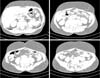

There were no significant changes in her laboratory tests. A computed tomography (CT) scan of the neck was performed (Figure 2), which showed prominence of adipose tissue in the cervical subcutaneous tissue, more pronounced in the submandibular, posterior cervicodorsal supraclavicular regions. Chest CT (Figure 3) showed prominence of adipose tissue in the subcutaneous tissue of the breast, anterior chest wall and dorsal region, including between the muscular planes, with a swelling effect. Abdominal CT showed prominence of adipose tissue in the abdominal subcutaneous tissue (Figure 4).